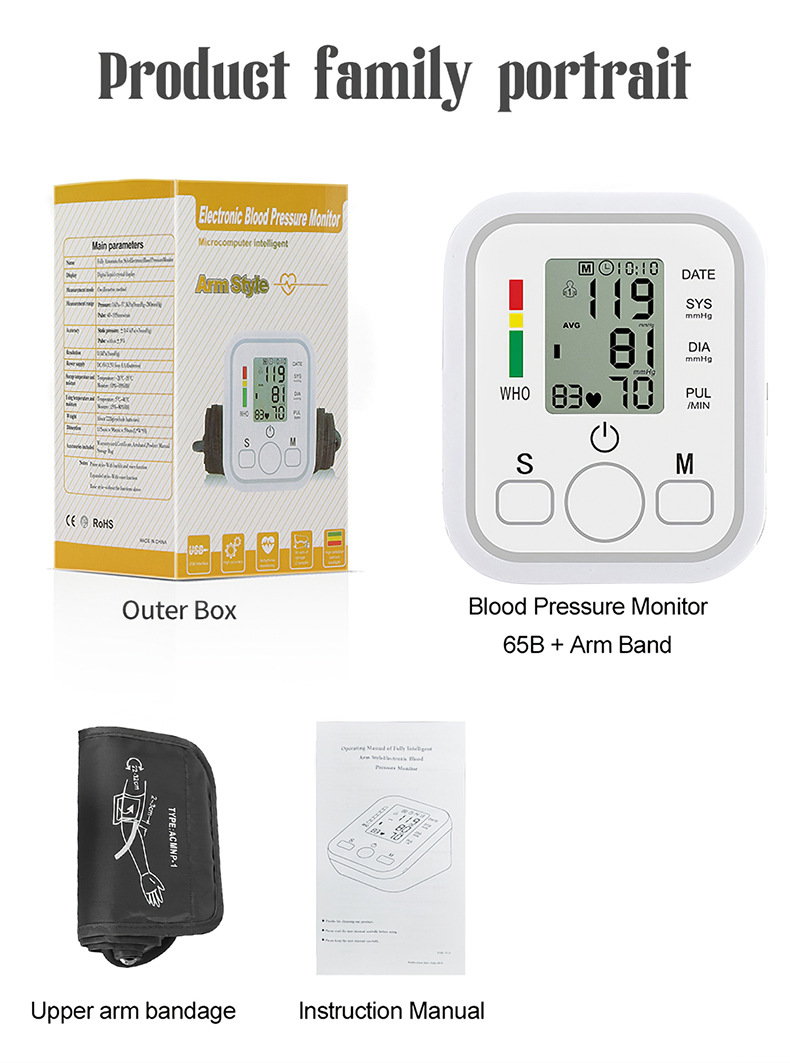

Packing list:

Arm strap+host+instruction manual

Product Image: